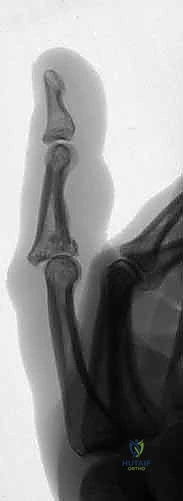

3. إدخال السلك المحوري (Axis Pin) - الخطوة الأهم

هذه هي الخطوة الأكثر حرجاً في العملية. يجب على الجراح تحديد مركز دوران مفصل PIP بدقة متناهية (Center of Rotation). يتم إدخال سلك معدني دقيق (K-wire) عبر رأس السلامية الدانية تماماً في مركز اللقمتين. إذا تم وضع هذا السلك بشكل خاطئ ولو بمليمترات، فإن المفصل سيتعرض للشد غير المتكافئ أثناء الحركة مما يؤدي إلى فشل العملية. يستخدم الدكتور هطيف جهاز الأشعة المرئية (Fluoroscopy - C-arm) داخل غرفة العمليات لضمان دقة لا تشوبها شائبة.

4. إدخال أسلاك الشد (Traction Pins)

يتم إدخال سلك آخر في السلامية الوسطى، بعيداً عن منطقة الكسر المفتت. هذا السلك هو الذي سيتم استخدامه لسحب السلامية الوسطى وإبعادها عن السلامية الدانية لتطبيق مبدأ "الشد الأربطي".